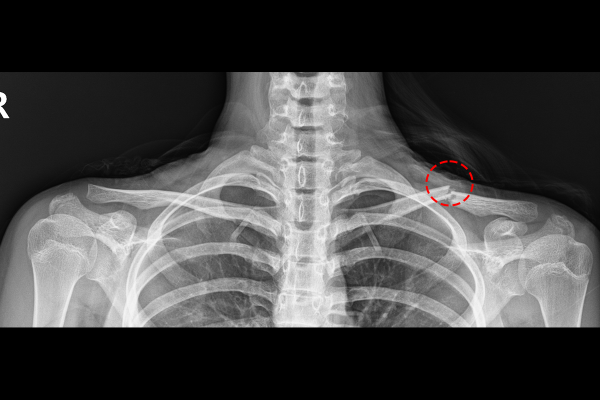

환자분의 쇄골 상태를 정확하게 파악하기 위해 X-RAY 촬영을 시행하였고, 검사 결과, 부러진 쇄골 뼈가 어긋나면서 살을 누르고 있는 것이 확인되어 소아(소아청소년) 쇄골 골절(Fx. clavicle shaft Lt.)을 진단하였습니다.

b72968fc2915dd5bd436116d60cd6556_1767918754_5433.png